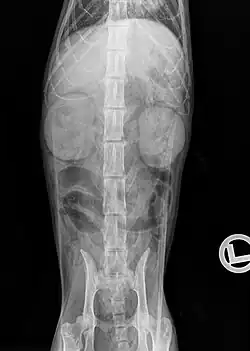

Urography: Diffuse accumulation of contrast medium in the kidneys of a cat with high-grade CNE

An X-ray examination can be used to detect changes in the size, density and position of the kidneys as well as some urinary stones (struvite and calcium oxalate stones are "radiopaque") and soft tissue calcifications. In severely emaciated cats or fluid accumulations in the retroperitoneal space, however, the kidney can only be visualized to a limited extent on the X-ray image due to the resulting reduction in contrast. Excretory urography, in which a radiopaque contrast medium (e.g. Iopamidol, Iohexol) is injected into the bloodstream and its excretion via the kidneys is recorded radiographically. This makes it possible to detect circulatory disorders, dysfunctions of the renal corpuscles and obstructions of the outflow pathways.[22]